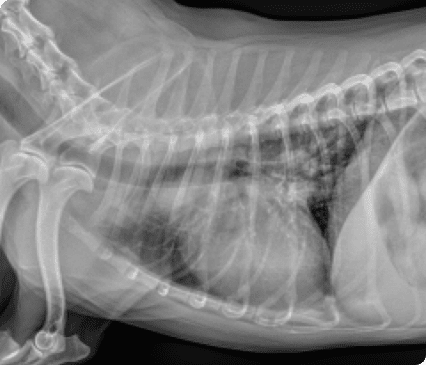

대학병원급 영상장비와 내과·외과 협진 시스템을 갖추고 있으며, 초기 무증상부터 중증 질환까지 체계적이고 종합적인 관리가 가능합니다.

일산시티동물의료센터는 최신 고해상도 초음파 장비를 통해 세밀하게 심장을 정밀하게 분석하여 심장질환을 진단합니다.